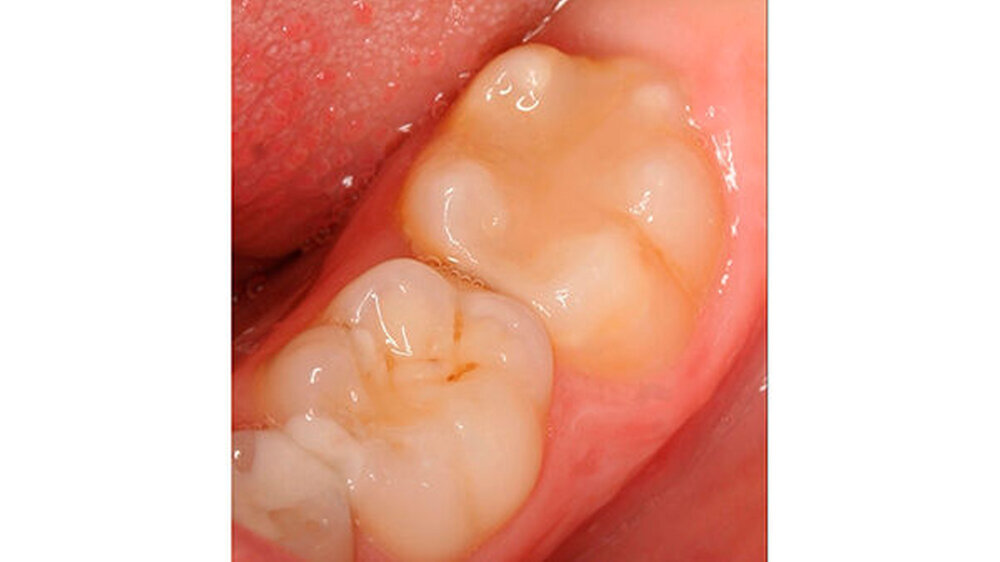

Bei einigen Patienten bestand allerdings auch schon im Milchgebiss eine Neigung zu Hypomineralisationen (Abbildung 3), klassifiziert wurden diese inzwischen als MDH (=deciduous molar hypomineralization) [Elfrink et al., 2012]. Inwiefern eine Hypomineralisation im Milchgebiss aber tatsächlich einen Indikator für eine MIH im bleibenden Gebiss darstellt, ist bisher nicht genauer zu beschreiben [Elfrink et al., 2012].

Die Behandlung der MIH stellt an Patienten und Behandler dadurch ganz besondere Herausforderungen, denn zu der Schmerzempfindlichkeit/Überempfindlichkeit der Zähne kommt die in der Regel schlechte Anästhesierbarkeit der betroffenen Zähne hinzu [Steffen & van Waes, 2011]. Die Behandlungsnotwendigkeit im Durchbruch erschwert das Kavitätendesign, die Trockenlegung und die Wahl des Füllungsmaterials erheblich [Lygidakis et al., 2010]. Aber auch nach vollständigem Durchbruch bleibt die Frage des Kavitätendesigns und der erforderlichen Restauration bestehen [Lygidakis et al., 2010].